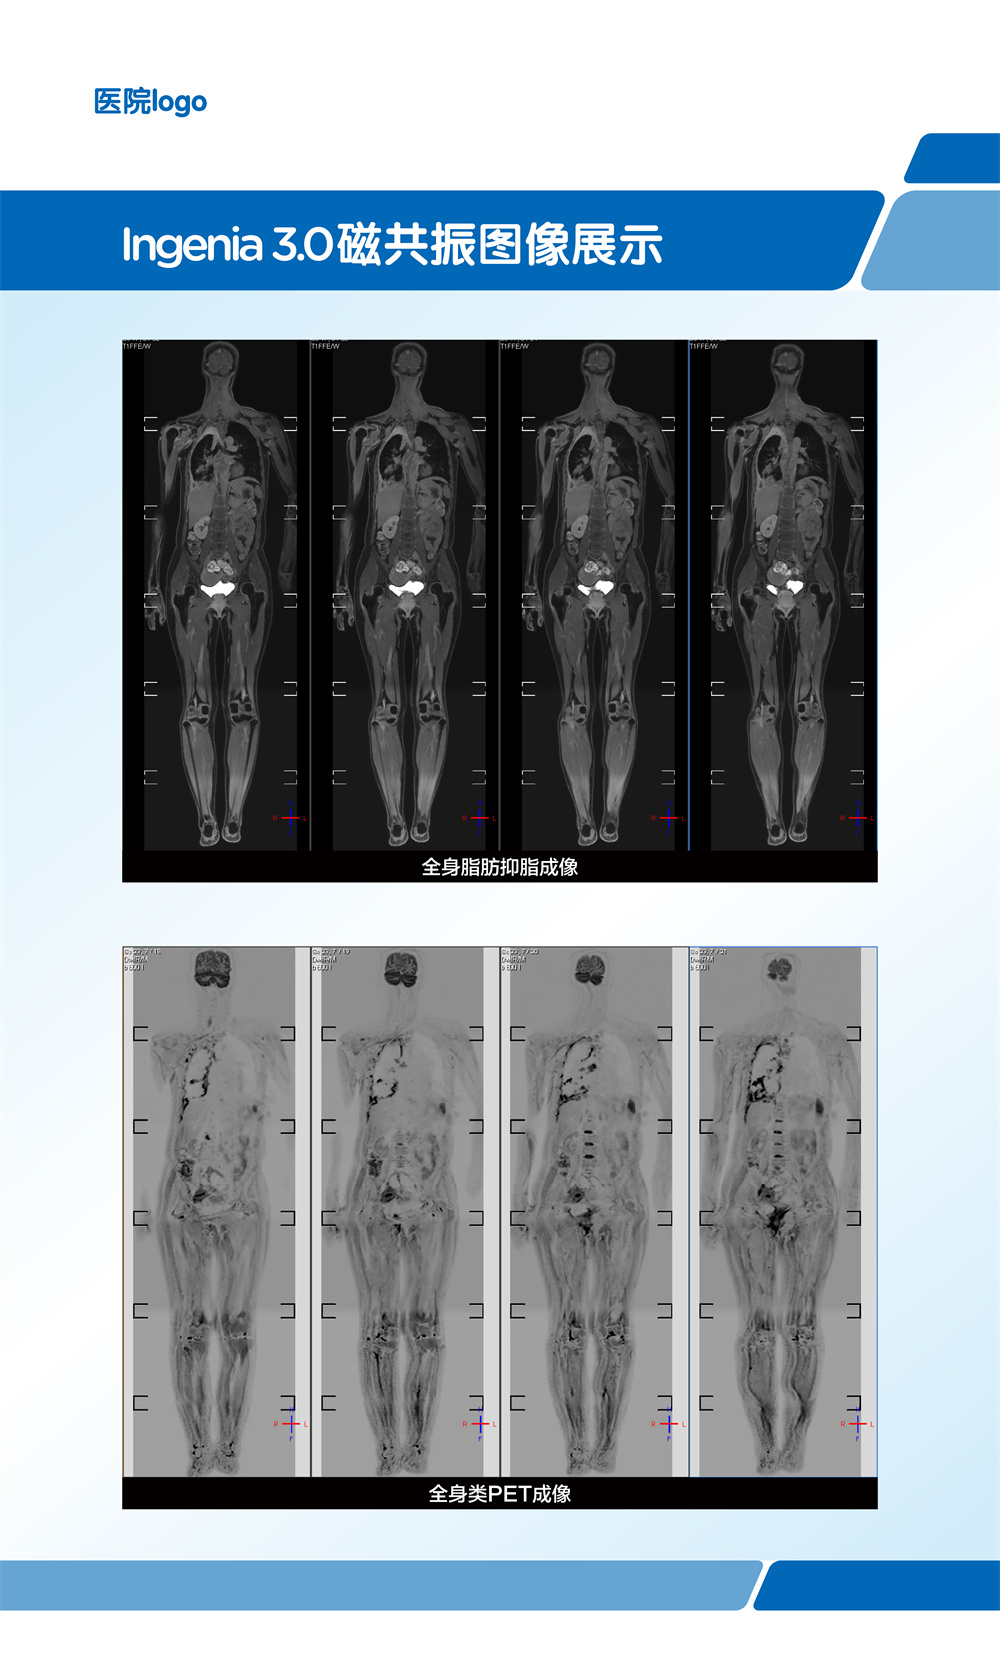

飞利浦大孔径光速Ingenia 3.0T磁共振是业内唯一同时具备"全数字高清成像平台和四维多源射频发射成像平台"的高端3T磁共振,具有病人检查舒适,扫描速度快,图像分辨率高的特点。在神经系统,骨肌系统,体部系统包括心脏和腹部等都有良好的应用和独到优势,为疾病的诊断及治疗提供更可靠、更丰富的信息,对于脑卒中和胸痛等中心的建设起到重要的作用。设备具备飞利浦独有的全数字线圈,可以实现三维全心不打药冠脉成像,无电离辐射和造影剂过敏风险,精准显示冠脉狭窄,有效排查临床无意义的冠脉狭窄(准确度达90%)。

在全身弥散加权成像的同时,可进行磁共振全身扫描,增加肿瘤检出敏感性。

临床应用范围:寻找恶性肿瘤原发灶;恶性肿瘤分期;全身转移灶筛查;淋巴结转移筛查;术后放化疗疗效监测;恶性血液肿瘤疗效观察;体检与肿瘤筛查。